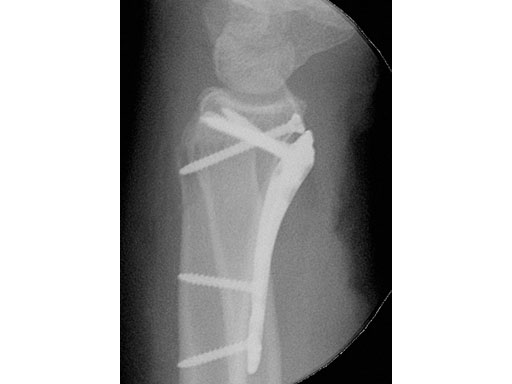

Fig 3ac Immediate postoperative x-rays.